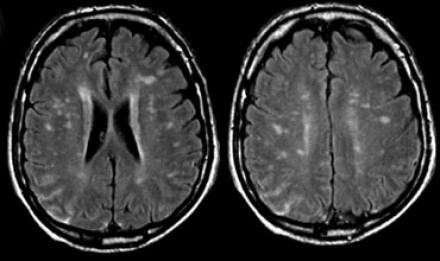

圖片一

在上圖中,是各種多發(fā)性點狀和斑塊狀白質(zhì)病灶圖像,我們對其中部分病例進行詳細討論。需要說明的是,以下鑒別診斷中提到的疾病與上圖中的圖像并不完全重合。

交界區(qū)腦梗死

MRI成像病灶要點:一般來說,這些病灶僅位于一個腦半球,要么位于深層白質(zhì)與灰質(zhì)的分水嶺區(qū)域(watershed area),要么位于周圍的分水嶺區(qū)域。在上圖中,病灶位于深層的分水嶺區(qū)域。

急性播散性腦脊髓炎(ADEM)

MRI成像病灶要點:在感染或接種疫苗后10-14天,多個局灶性病灶出現(xiàn)在腦白質(zhì)和基底節(jié)。與MS一樣,ADEM病變可累及脊髓、U形纖維以及胼胝體,有時可出現(xiàn)增強病灶。與MS所不同的是,ADEM的病灶通常更大,且好發(fā)于青年人,病程是單相的。

萊姆病

病灶大小約為2-3毫米,與MS的病灶相似,但患者會有皮疹和其他流感樣疾病。脊髓呈現(xiàn)高信號,CN7(神經(jīng)根入腦干區(qū))信號增強。

肉樣瘤

肉樣瘤的病灶分布與MS非常相似。

進行性多灶性白質(zhì)腦病(PML)

PML是一種由JC病毒感染引起的脫髓鞘性疾病,常見于免疫抑制患者。

MRI成像病灶要點:白質(zhì)損傷病灶在U形纖維的間隙占位,不增強,與HIV或CMV不同。

PML的病灶可在單側(cè)出現(xiàn),但更常見的是呈雙層、不對稱性分布。

血管周圍間隙(Virchow Robin spaces)

MRI成像病灶要點:T2加權(quán)成像明亮,F(xiàn)LAIR成像黑暗。

小血管性疾病

白質(zhì)損傷病灶位于深層白質(zhì)區(qū)域,不位于胼胝體、腦室旁或皮層旁。